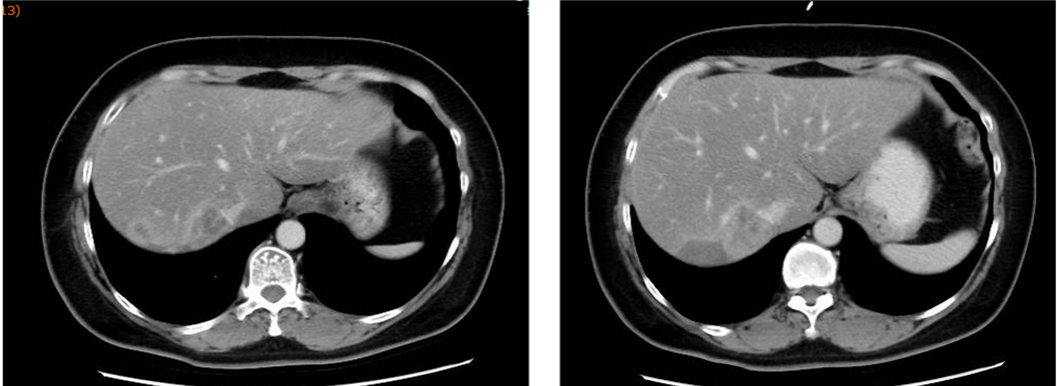

▌六线治疗:

2020-12-22始行吉西他滨+曲妥珠单抗(汉曲优)+帕妥珠单抗治疗,具体:吉西他滨1g/m2 1.6g d1、1.8g d8;曲妥珠单抗首次 8mg/kg 520mg,以后6mg/kg 390mg,帕妥珠单抗首次840mg,以后420mg,d1,Q21d;自第10周期开始双靶维持治疗。2021-03-25复查:肝内多发转移较前减少、缩小(较大24x20mm→12x11mm),肝门区及门腔间隙淋巴结缩小(28*18mm→12*7mm),左侧肋骨转移减轻),最佳评效PR。2021-12-15头MRI示可疑脑膜转移,评效PD,PFS为12月。不良反应:手足麻木2度,肝功损伤2度。

图7 六线治疗